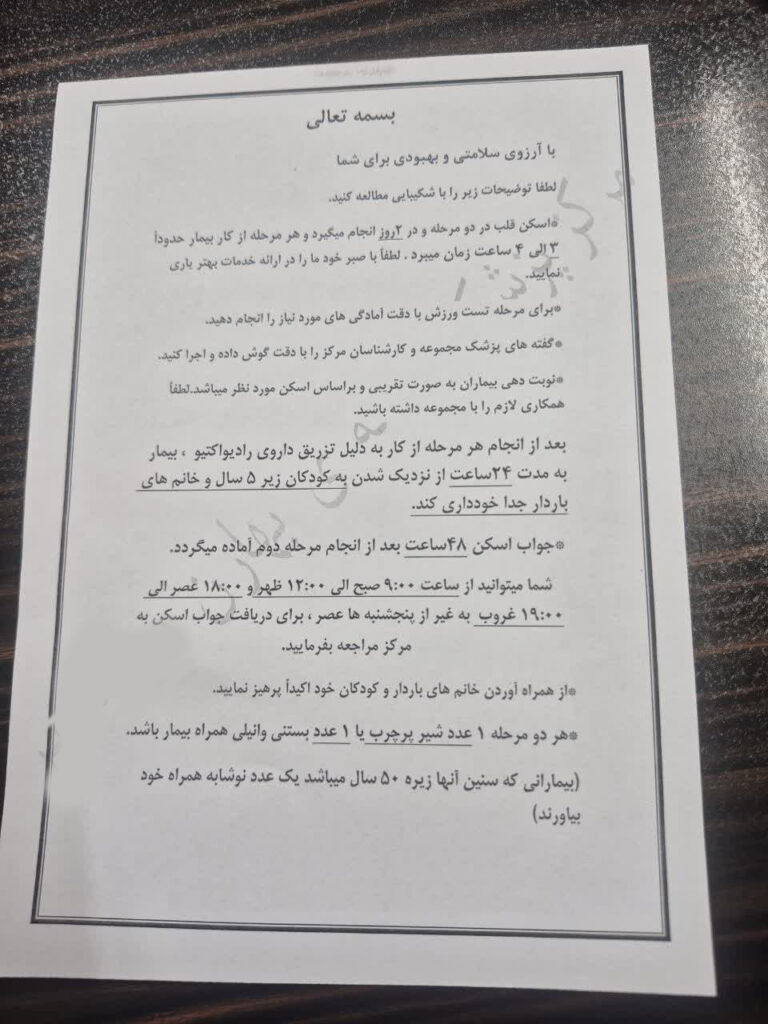

فرمهای زیر مربوط به مراحل آمادگی بیماران پیش از انجام اسکن قلب هستند.پیش از انجام اسکن قلب، لازم است فرمهای زیر را بهمنظور آمادهسازی و بررسی اولیه تکمیل کنید.

باید در نظر داشت که اسکن هستهای قلب معمولاً یک فرآیند یکساعته نیست. این آزمایش به صورت دو مرحلهای (مرحله استراحت و مرحله فعالیت یا استرس) انجام میشود. در برخی موارد، بر اساس پروتکلهای پزشکی و شرایط فیزیکی بیمار، ممکن است بین این دو مرحله چند روز فاصله زمانی نیاز باشد. بنابراین، بیمار نباید انتظار داشته باشد که در یک روز تمام مراحل طی شود و جواب نهایی را دریافت کند.

پس از اتمام مراحل تصویربرداری، تصاویر باید توسط متخصص پزشکی هستهای بازبینی و تحلیل شوند. استخراج نتایج دقیق و نوشتن گزارش نهایی نیز به زمان نیاز دارد که معمولاً بین 24 تا 72 ساعت پس از اتمام آخرین مرحله اسکن طول میکشد.